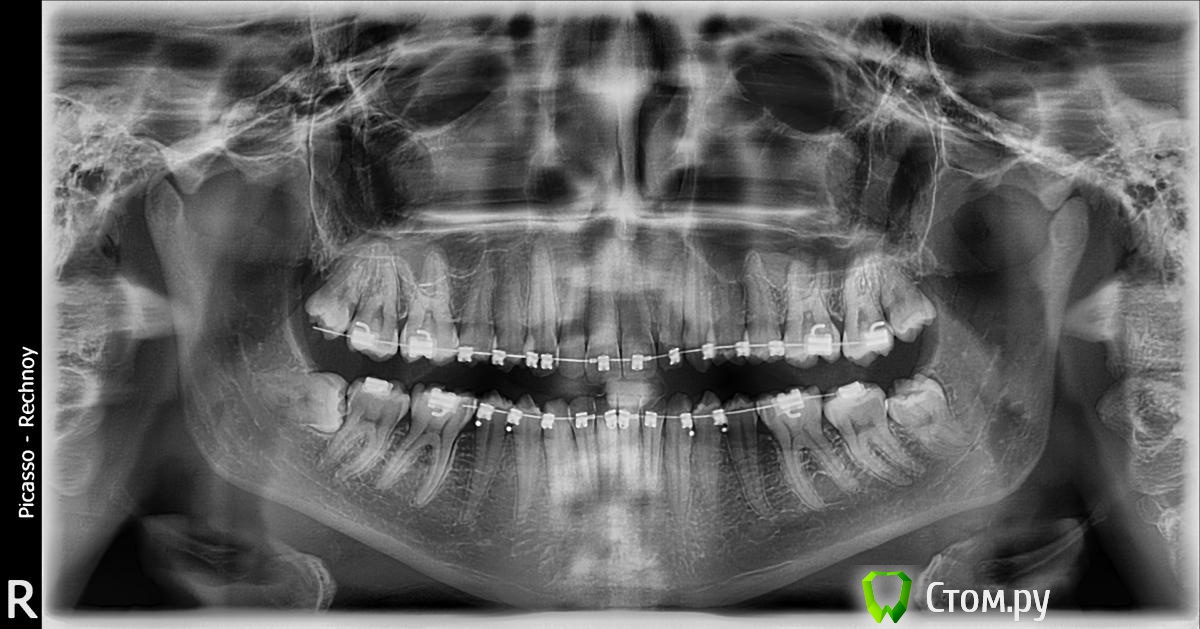

Ношу брекеты суммарно около года. Врач планирует заканчивать лечение через месяц-два - говорит, что зубной ряд ровный и что пора ставить жесткую стальную дугу.

Мне текущее положение вещей не очень нравится - какой-то некрасивый "наклон" зубов, очень разное расстояние от верхней губы до десны на всех зубах. В общем, сильная асимметрия, на мой взгляд.

Если нужны какие-то еще фотографии, постараюсь сделать и приложить. Сейчас есть рентгеновские снимки зубов, но они старые, полугодовой давности. Зубы мне не удаляли.

PS В самом деле, брекеты ношу уже окло трех лет, но два года "вхолостую", т.к. в студенческие годы просто не было денег на это дело. Врач говорит, пора снимать брекеты, зубы устали. Система damon 3.